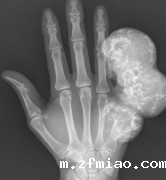

骨密度检测仪器提醒疼痛难忍,他被诊断出患有骨肉瘤。80岁的朱爷爷被诊断出患有纤维肉瘤,因为他担心右腿后面不断增长的软组织肿块。80岁的朱爷爷被诊断出患有纤维肉瘤,因为他...